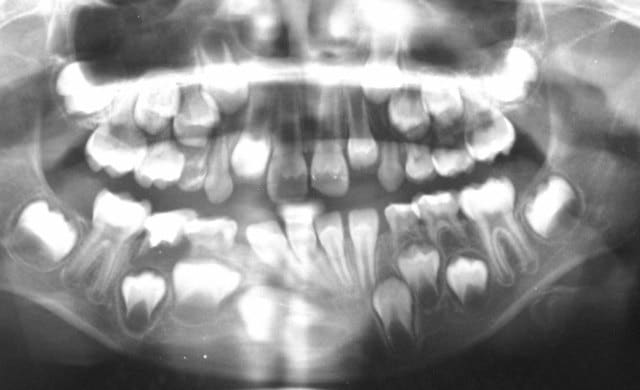

Voici un cas que j’envisage de traiter, tout au moins au départ, je dirais à la Dancha.

C'est-à-dire sans matériel O.D.F.

Que proposerais tu ?

D'abord de refaire une bonne panoramique...

Aussi voici la pano au maximum de définition permis par Eugenol.

@+ Bjc.